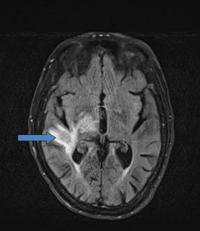

Dada la posibilidad de afectación del SNC en el momento del diagnóstico, es esencial realizar una resonancia magnética craneal con contraste y una evaluación del líquido cefalorraquídeo para valorar la existencia de lesiones en el SNC (

Figura 7).

Figura 7. Imagen de resonancia magnética de un linfoma cerebral.